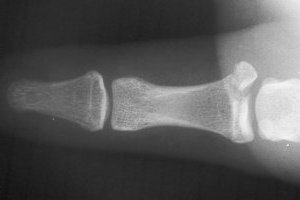

Injuries associated with a large avulsion fracture can be repaired with one or two micro screws, as was done here:

Click for larger image